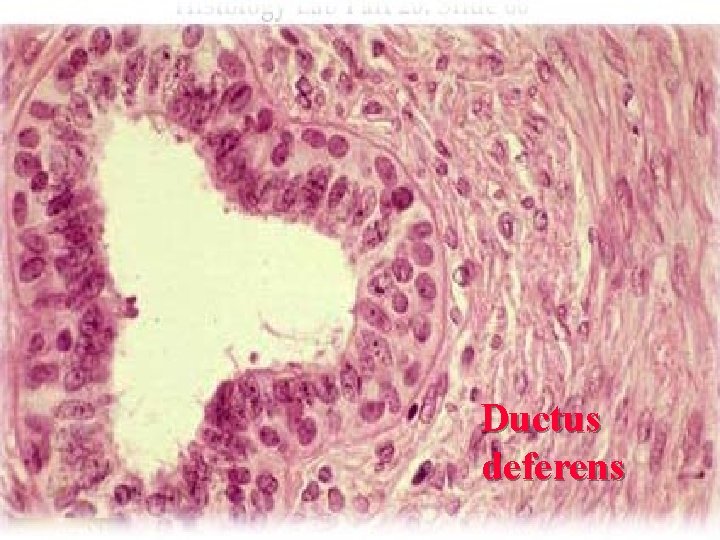

三 ductus deferens lmucosa+muscular wall + adventitia lpseudostratified ciliated columnar Epi. =principal C + basal Cinner lmuscular wall : longitudinal, middle circular, outer longitudinal SMC

Ductus deferens

Ductus deferens